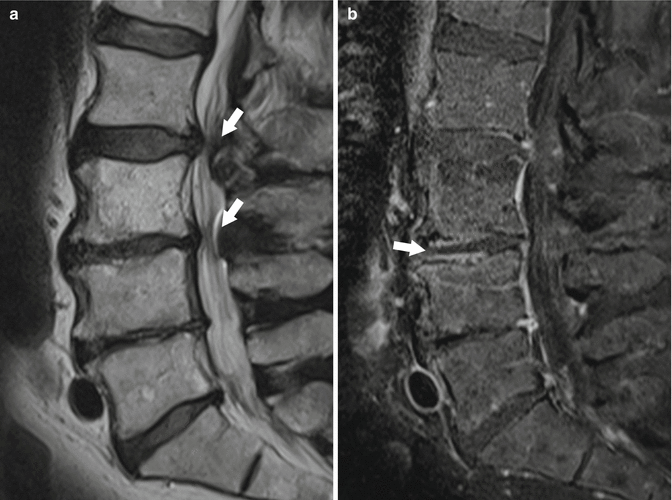

From radiologykey.com

Degenerative Diseases of the Spine Radiology Key Vacuum Disc Phenomenon L2-L3 Recently, this phenomenon has gained interest due to a relatively new surgical technique called percutaneous discoplasty, aimed at treating low back pain secondary to degenerative disc disease in elderly patients. Vacuum disc phenomenon is the accumulation of gas within the intervertebral discs, often a sign of advanced disc degeneration. While vacuum disc phenomenon may be. Vacuum disc phenomenon is seen. Vacuum Disc Phenomenon L2-L3.